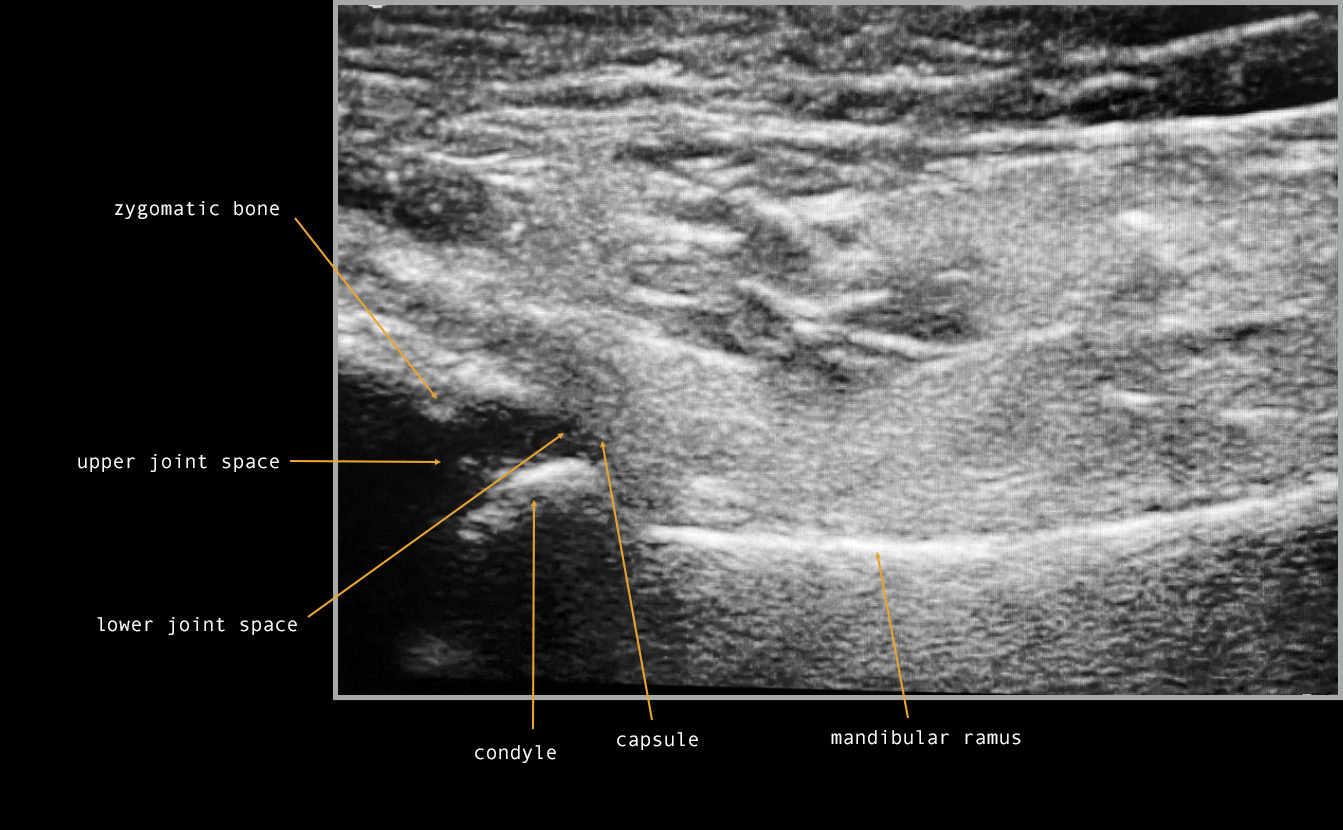

The TMJ area has some particularities, including a small examination area, limited access to deep structures and a high risk of sound reflecting from the bone tissue, which can make image interpretation very complex.38 Soft tissue visualization is severely limited by bone, as sound energy is almost completely absorbed by soft-tissue interfaces and the bone tissue. Thus, the external placement of the transducer enables only the acquisition of the lateral third of the joint, and only in the axial and coronal planes.37 Therefore, the main disadvantage of US in the TMJ area is the limited imaging of the upper and medial parts of the condyle and the disk; these structures are hidden by the acoustic shadowing caused by the rebounding and absorption of US waves by the zygomatic bone.12, 19, 20, 42 The TMJ images produced by US depend on the echogenicity of tissues as follows: the condylar head and the articular eminence are hypoechoic and appear black39; the bone margins are hyperechoic and appear white39; the connective and muscular tissues are isoechoic (an intermediate reflection of sound waves) and appear heterogeneously gray23, 39; the joint capsule surface is highly reflective of sound waves, creating a hyperechoic line (white)11, 23, 39, 42; the articular disk appears as a thin, hypo-to-isoechoic, homogeneous band11, 23, 42; articular fluid-filled spaces are hypoechoic and appear black,11, 23, 42 although these are virtual cavities that are generally not detectable unless joint effusion is present38; bone marrow is usually hypoechoic and appears black.38

In most publications, TMJ US monitoring is based on the standardized protocol of Emshoff et al.43 Most studies have adopted similar protocols, which include transversal and longitudinal scans to evaluate the joint compartments in the coronal, axial and oblique planes (Figure 2).41 During the longitudinal scanning, the probe is placed over TMJ, perpendicular to the zygomatic arch and parallel to the mandibular ramus, and inclined until the best view is achieved; then static and dynamic evaluations are performed (Figure 3).38 The performance of the US diagnostics is outside the scope of the present review and has been extensively described for 3 main diagnostic domains: disk displacement; joint effusion; and cortical erosion.38, 40, 41, 42, 44 It has been suggested that US can complement a clinical examination as an initial evaluation tool.40